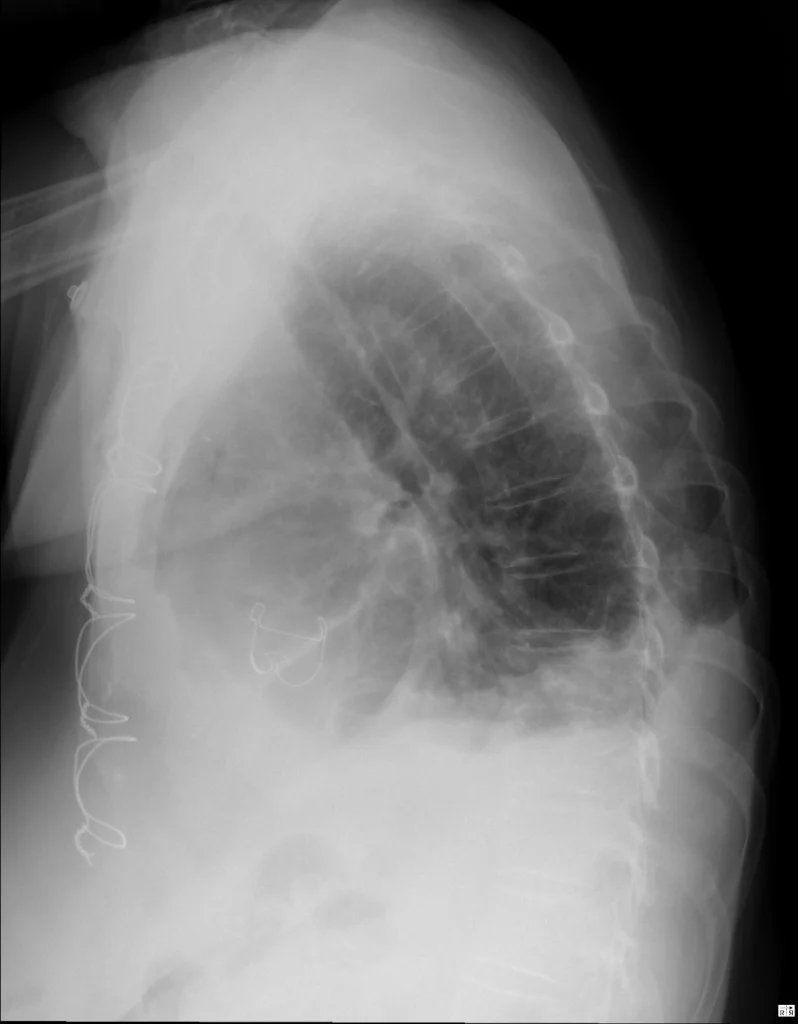

Rx de tórax L. El seno costofrénico posterior es, estrictamente hablando, el más declive. En la radiografía lateral, ambos (derecho e izquierdo) están ocupados por material radiopaco, indicando derrame pleural bilateral. Otros hallazgos: sutura metálica esternal; válvula aórtica protésica

Los SCF laterales pueden seguir siendo agudos sí el derrame pleural es de pequeño volumen (menos de 200 cc). Si la sospecha es alta, evalúa en la proyección lateral los SCF posteriores. Recuerda que anatómicamente, estas son realmente las áreas más declives de los pulmones y del espacio pleural.